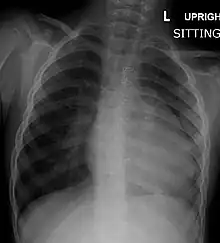

A CXR (Chest X-Ray) of a child with tetralogy of Fallot

Before more sophisticated techniques became available, chest x-ray was the definitive method of diagnosis. The abnormal "coeur-en-sabot" (boot-like) appearance of a heart with tetralogy of Fallot is classically visible via chest x-ray, although most infants with tetralogy may not show this finding.[37] The boot like shape is due to the right ventricular hypertrophy present in TOF. Lung fields are often dark (absence of interstitial lung markings) due to decreased pulmonary blood flow.[15]: 171–72